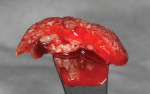

In patients or sites that are challenged, the use of bioactive materials may be beneficial to obtain improved physical and/or biologic results. In 2019, Dragonas and coworkers completed a literature search on various formulations and methods of fabrication of platelet-rich fibrin (PRF) and the effect on bone formation in different indications.18 Based on the literature, they could not conclude that there was an improvement in ridge preservation, augmentation (based on histomorphometric evidence), or bone quality in sinus augmentation. Miron et al reached similar conclusions in 2017.19 However, incorporation of PRF (Intra-Spin®, BioHorizons, biohorizons.com) does decrease washout of graft particles due to the ability to form "sticky bone" or "bone blocks" (Figure 4),20,21 provide anti-infective capabilities,22 and can enhance soft-tissue closure over the site.23